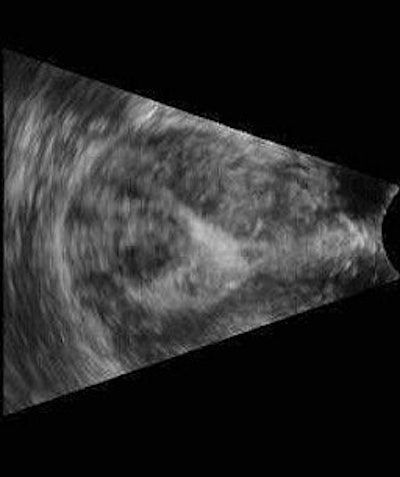

![]() |

| Three-dimensional ultrasound images showing submucosal fibroids. Images courtesy of Dr. Beryl Benacerraf. |

Other instances in which 3D is helpful include identifying the presence and nature of submucosal fibroids, effectively performing a "virtual hysteroscopy."

In one study of 43 patients with abnormal uterine bleeding, Benacerraf and colleagues found that a 3D coronal view of the uterus was helpful in detecting polyps or fibroids in 35% of cases. The polyps were suggested but ill-defined on 2D ultrasound, she said, and 3D clarified the findings.

The same study also found that turning on the 3D capability wasn't necessary or worthwhile if the 2D scan appeared normal or showed a well-defined finding.